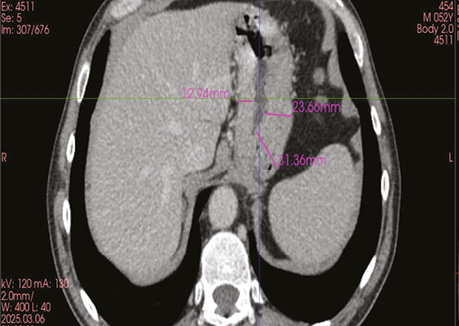

Хворого перекладено на спину. Виконано мінілапаротомію. Остаточно мобілізовано та відсічено шлунок (рис. 4). Відсічено голодну кишку на відстані 20 см від звʼязки Трейца. Скелетизовано 10 см голодної кишки. Після 10 хв очікування — трансплантат життєздатний. Заведено в торакальну порожнину. Сформовано ентеро-ентероанастомоз. Накладено пошарові шви на рану. Хворого повторно перевернуто в положення на лівий бік. Виконано торакотомію по попередній рані. Сформовано езофагоюєноанастомоз кінець у бік [11] (рис. 5).

Рис. 4. Післяопераційний препарат